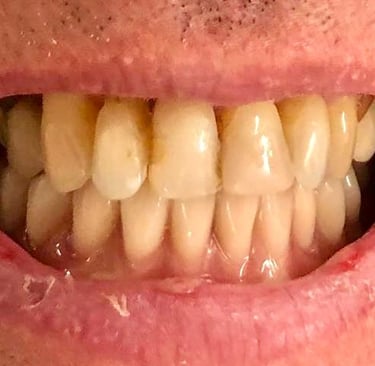

Aspecto Clínico Inicial - Fotografias originais — nenhuma contém retoques

Antes